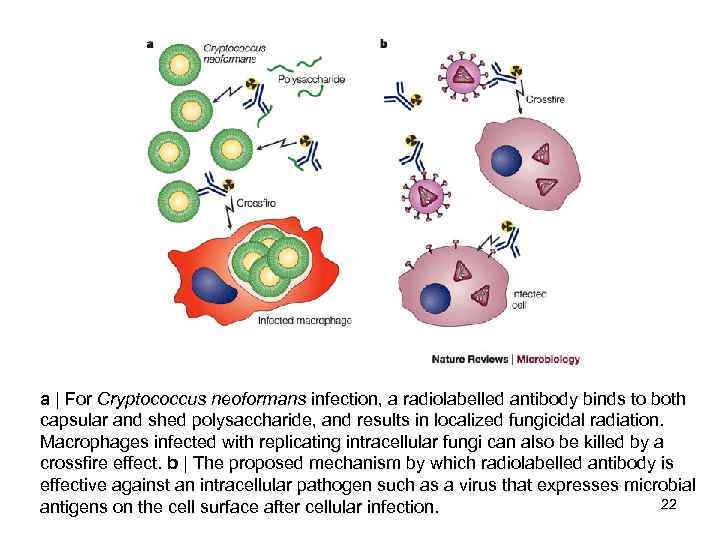

a | For Cryptococcus neoformans infection, a radiolabelled antibody binds to both capsular and shed polysaccharide, and results in localized fungicidal radiation. Macrophages infected with replicating intracellular fungi can also be killed by a crossfire effect. b | The proposed mechanism by which radiolabelled antibody is effective against an intracellular pathogen such as a virus that expresses microbial 22 antigens on the cell surface after cellular infection.

a | For Cryptococcus neoformans infection, a radiolabelled antibody binds to both capsular and shed polysaccharide, and results in localized fungicidal radiation. Macrophages infected with replicating intracellular fungi can also be killed by a crossfire effect. b | The proposed mechanism by which radiolabelled antibody is effective against an intracellular pathogen such as a virus that expresses microbial 22 antigens on the cell surface after cellular infection.